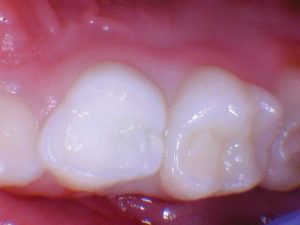

Figura 1. Después del ataque ácido y el uso del agente de unión Scotchbond Universal (3M), los dos molares primarios superiores se restauraron con Activa Bioactive Restorative A2. |

Figura 4. El seguimiento de 18 meses no mostró fracturas y márgenes intactos. |